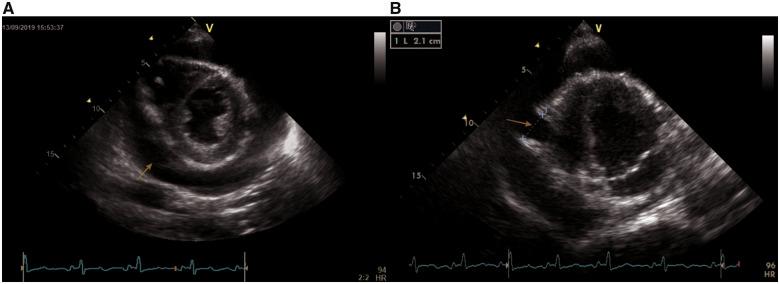

Right ventricular aneurysms (RVAs) are rare. We present a case with a combined RVA and right ventricular pericardial fistula resulting in a pericardial effusion and cardiac tamponade. The RVA was detected 47 days after the patient suffered a gunshot wound. This report adds to the body of scarce literature on RVA aetiology, diagnoses, and treatment.

A 30-year-old male patient presented with worsening respiratory distress over a 7-day period with clinical signs of cardiac tamponade following a history of a gunshot (with associated liver laceration, pulmonary embolism, right nephrectomy, and sepsis) 47 days prior. Transthoracic echocardiography showed a large circumferential pericardial effusion and an RVA. The patient was emergently taken for surgical repair of the RVA.